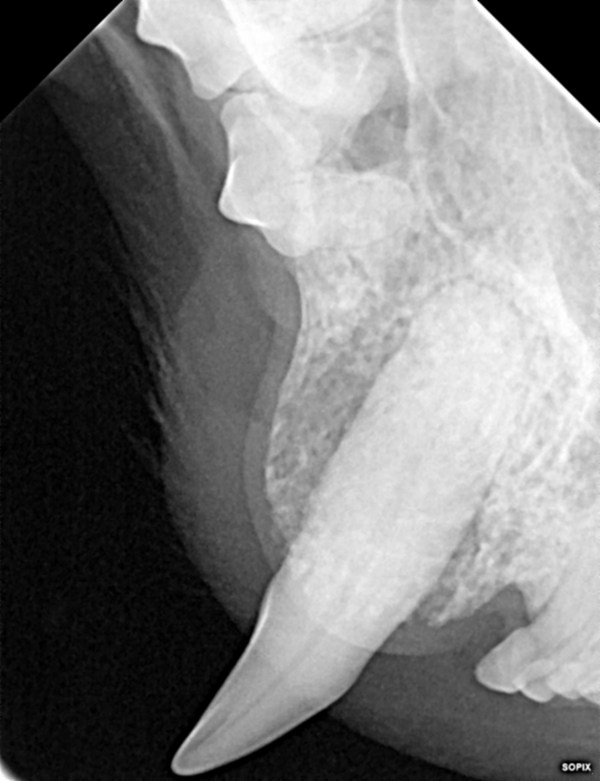

Im Zahnröntgen zeigte sich leider, dass obwohl nur die Spitze des Zahns abgebrochen war (roter Feil), das Lebendige des Zahns (die Pulpa) betroffen war und der Zahn längst abgestorben war. Dies zeigt sich im Seitenvergleich durch eine erweiterte Pulpenkammer (blaue Markierung).

Dies kann man auch auf Cocos Dentalröntgen nachvollziehen.

In Vollnarkose fiel auf, dass der vierte Backenzahn innen gebrochen war (roter Pfeil). Im Dentalröntgen waren große Wurzelspitzenabszesse zu sehen (blaue Pfeile). Durch die Kronenfraktur waren Bakterien ins Innere des Zahns gelangt und hatten diesen inifziert. Dies ist sehr schmerzhaft. Leider haben Hunde keine Möglichkeiten Zahnschmerzen zu äußern, sie leiden also stumm. Auffällig wurde es erst als der Abszess nach außen sichtbar wurde, was bereits eine lange Leidensdauer voraussetzt. In diesem Fall war es nicht sinnvoll, den Zahn durch eine Wurzelkanalbehandlung zu erhalten. Daher zogen wir den Zahn (die drei Zahnwurzeln wurden separat entfernt, damit keine Reste im Kiefer verblieben) und verschlossen die Wunde mittels Naht. Betty erhielt noch einige Tage Antibiose und Schmerzmittel.